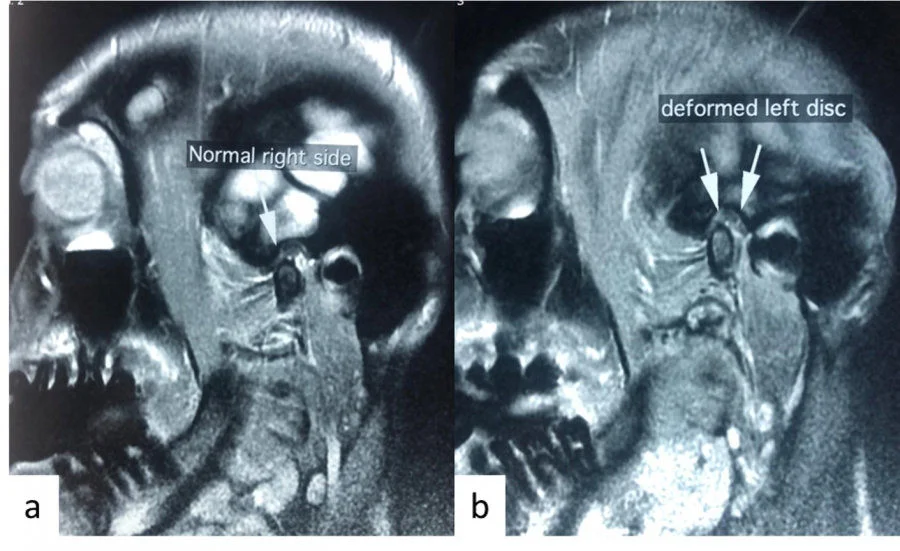

The temporomandibular joints (TMJ) are located in front of the ears. If you use your fingers to lightly press the recess in that place and open and close your mouth, you will feel the temporomandibular joint move. Muscle pain and joint disorders are the common causes of temporomandibular joint and muscle disorder (TMD). In the case of muscle pain, it may be related to parafunctions such as gum chewing, eating hard foods, clenching and tooth grinding at night. For joint disorders, it may be related to disc displacement and inflammation. There is a cartilaginous disc between the jaw bone and temporal bone of the TMJ.  If the disc becomes displaced, one may experience clicking or popping sounds during jaw function, and may contribute to pain in the TMJ or limited mouth opening. The pain may also spread to the head, face, or teeth etc.

Conventional approach to most types of TMDs begins with conservative treatment options, such as non-steroidal anti-inflammatory (NSAIDs), physiotherapy, soft diet and occlusal splint etc. When clinical improvement is not observed with conventional approach, arthrocentesis will be offered to patients with joint dysfunction. Arthrocentesis has been a standard treatment since the early 1990s, which involves the application of two small needles near the TMJ, and the joint is washed thoroughly with Normal Saline with the aim to clear the inflammatory substances and fibrous adhesion of the joints, and to reduce the negative pressure inside the TMJ. Arthrocentesis is a simple and safe treatment, which normally takes around 15-20 minutes in the clinical setting, with a high efficacy of 80-85%.